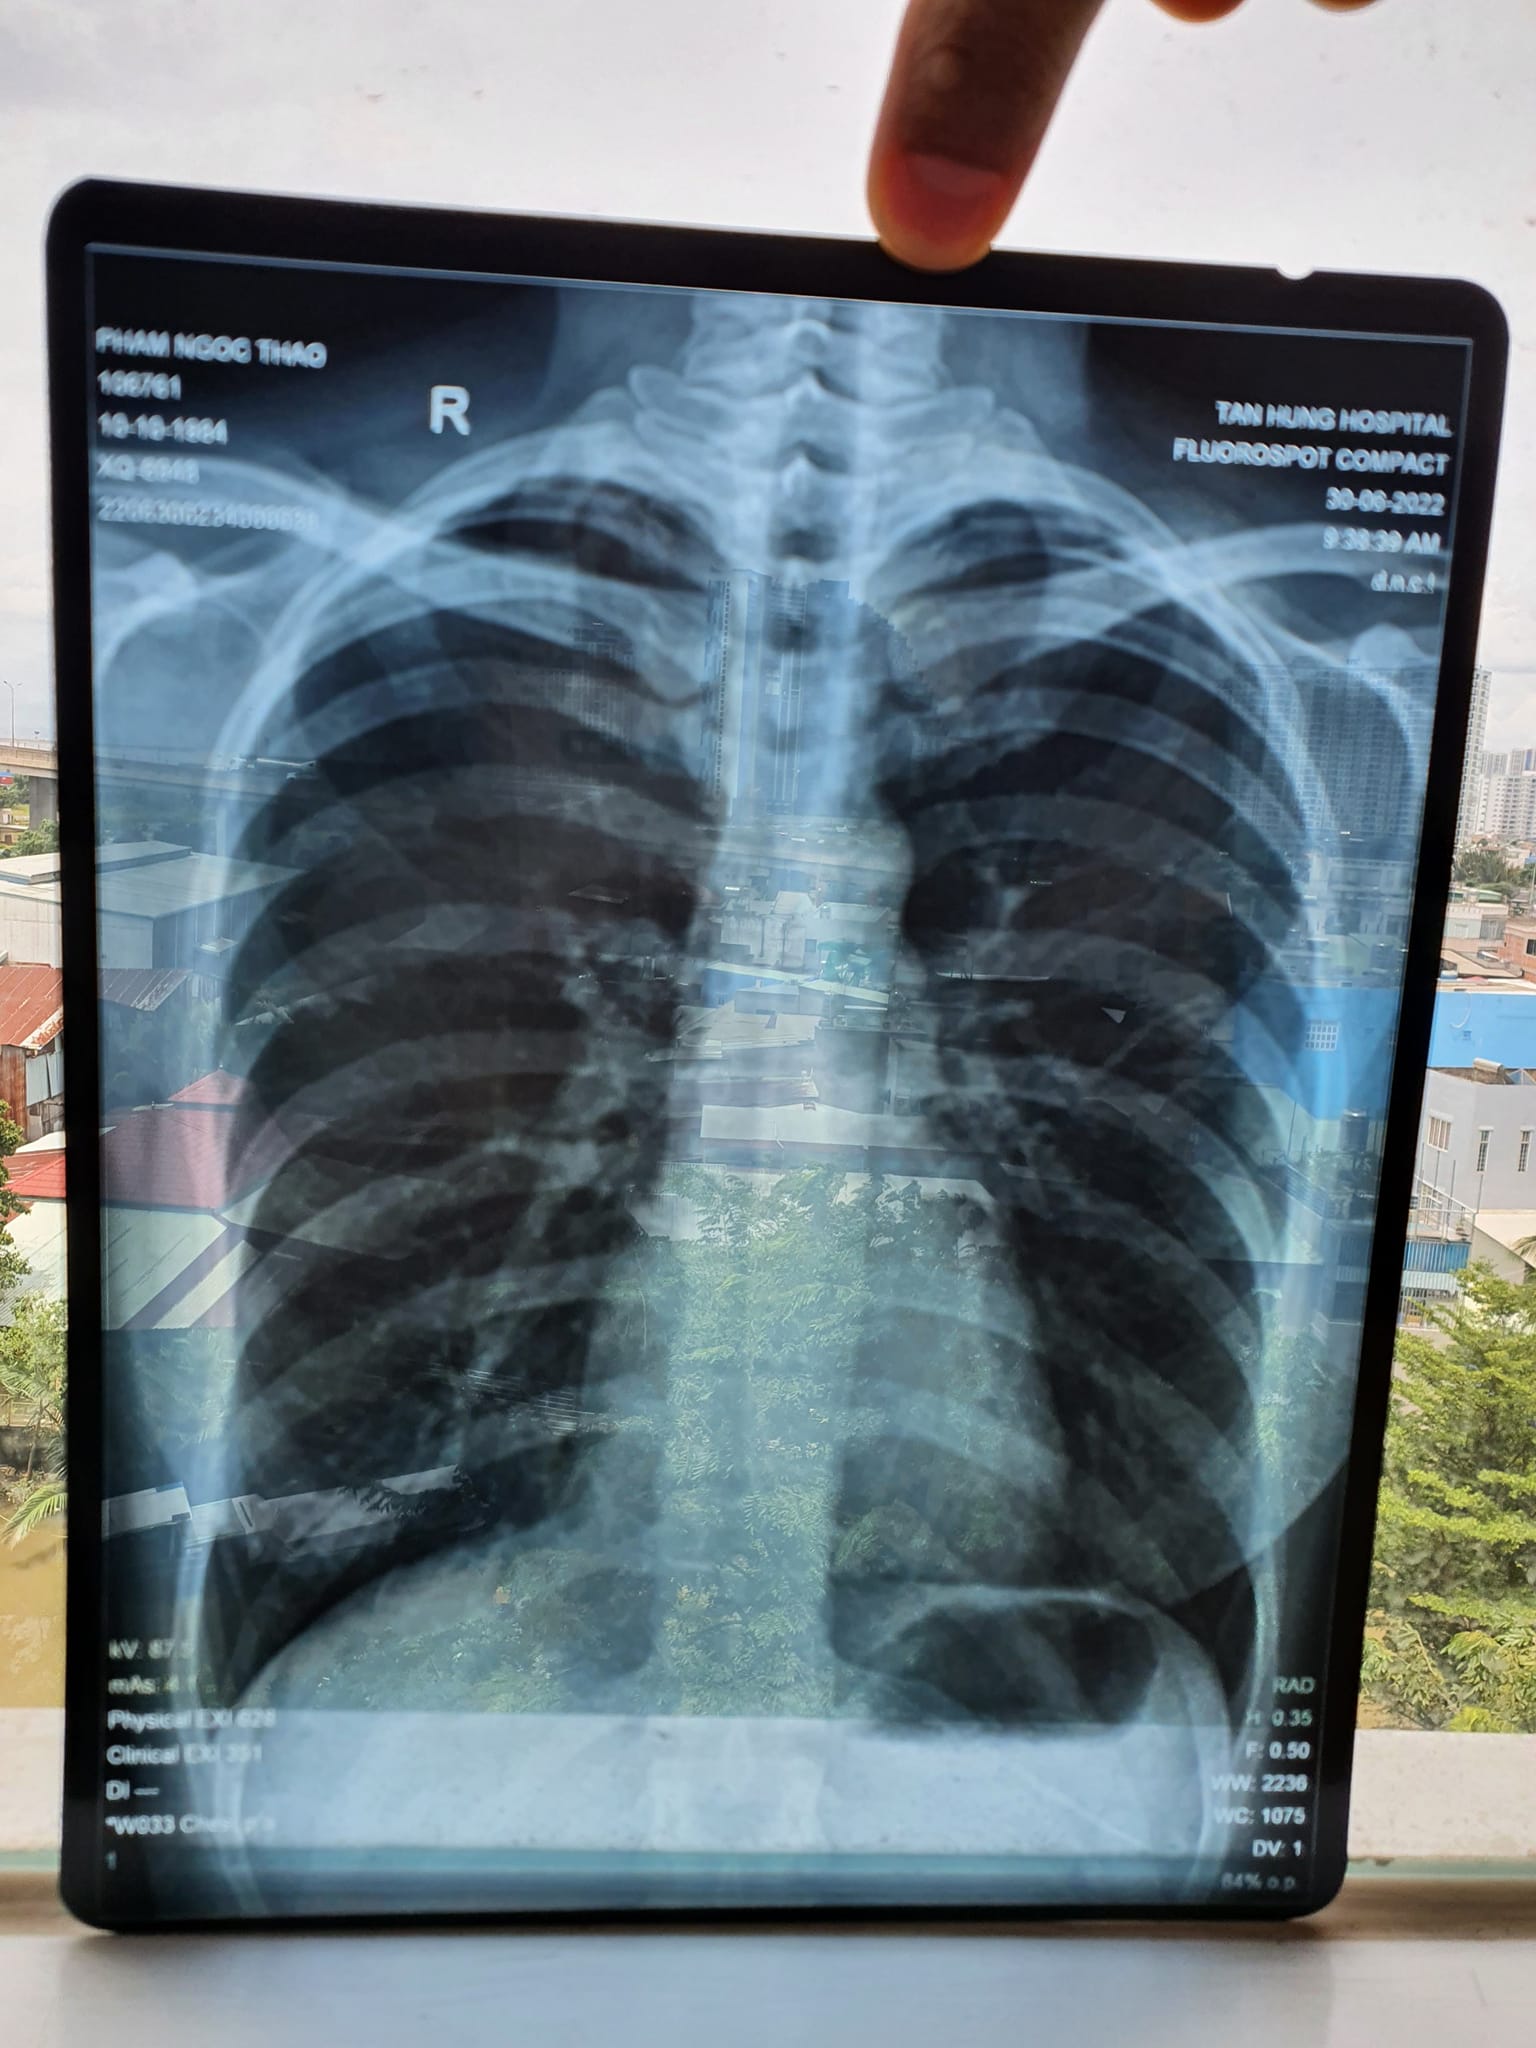

Kết quả X quang và CT sau khi chăm sóc sức khỏe bằng Năng lượng sinh học vào ngày 30/6/2022